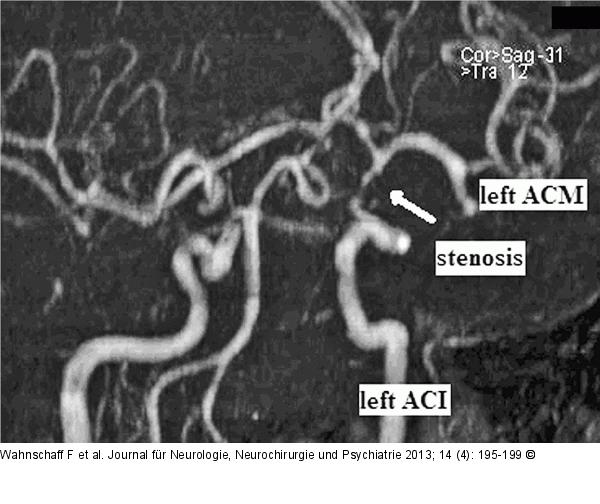

Abbildung 2: Hypophysenadenom Präoperative „Time-of-flight“- (TOF-) Sequenz mit Darstellung einer filiformen Stenose der linken Arteria carotis interna. |

Präoperative „Time-of-flight“- (TOF-) Sequenz mit Darstellung einer filiformen Stenose der linken Arteria carotis interna. |